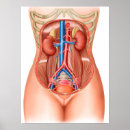

Carta do poster da anatomia do órgão interno do

Preço56,50 €

Impressão humano da anatomia dos órgãos interno

Preço15,60 €